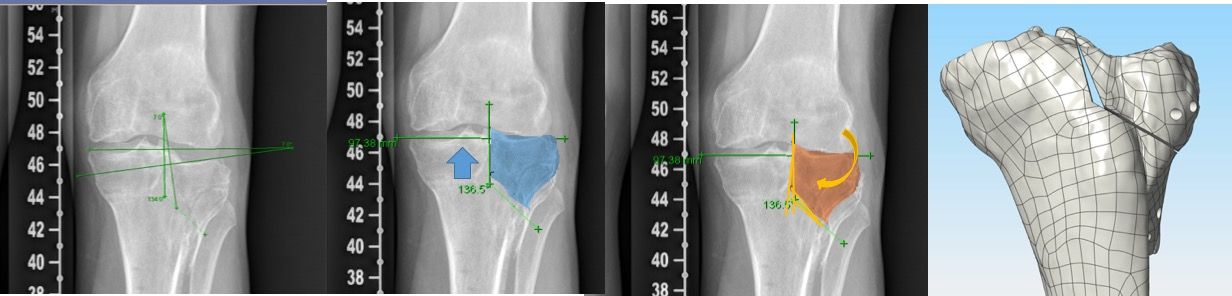

3D planning

The described conventional planning is focusing on the frontal plane only. PSCG includes the option of a much more sophisticated 3D planning procedure (Figure 1F).

Virtual osteotomy

This is one of the main advantages of the PSCG technique which allows a more sophisticated 3D planning.

Osteotomy correction depend on three connected parameters:

- Cutting plane angulation: This represents the angulation of the cutting plane with frontal and sagittal tibial mechanical axes (Figure 3). Every displacement of the sawing plane angulation away from a perfect perpendicular angle with the tibial mechanical axis and perfect parallel to the tibial plateau plane will influence frontal and sagittal correction.

- Hinge positions: A more posterior hinge will decrease the tibial slope and a more anterior one will increase the tibial slope as compared to more central positions (Figure 4)

- Wedge positions: A more posterior wedge will decrease the tibial slope and a more anterior wedge will increase the tibial slope as compared to more central positions.

Those three elements are used in the 3D preoperative planning to obtain the desired correction (Figure 5) and to modify intentionally MPTA and slope when needed.